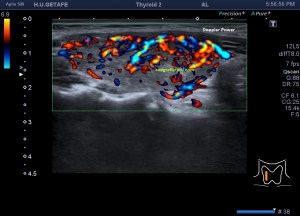

En la exploración objetivamos una glándula tiroidea aumentada de tamaño, sin imágenes nodulares, pero si heterógenea toda ella con afectación global en ambos lóbulos tiroideos. Semiológicamente se observa una y/o hiperplasia glandular y es muy significativo un abombamiento anterior de la glándula, con unas medidas elevadas discretamente respecto de sus medidas en rango de normalidad, es decir, la paciente tiene bocio no nodular y además alteración en la ecogenicidad de la glándula, pero lo más llamativo fue cuando puse el doppler para estudiar la vascularización de ambos lóbulos tiroideos. Era una vascularización elevada, mucho más que la normal vascularización de esta glándula. Es el conocido Infierno Tiroideo.

Lo primero, reconoce siempre la normalidad para poder identificar anormalidad. En la imagen 1 tienes una imagen normal de ambos lóbulos tioideos en un corte axial (nos sirve para repasar anatomía básica), en la imagen 2 un corte longitudinal de uno de los lóbulos con su vascularización típica. Bien guarda en tu cabecita estas dos imágenes y ponte en modo concentración para descubrir los cambios semiológicos en el caso de la paciente referida con anterioridad.

Cuando estudiamos concienzudamente la ecoarquitectura del Tiroides es momento de estudiar su apariencia vascular y descubro esto inmediatamente que me llama poderosamente la atención y que ves en la imagen 5, mira:

5

En la imagen 6 observas la misma imagen con el modo angio activado (doppler power), con el que vamos a conseguir observar la vascularización de flujo lento, por eso en el mismo corte puedes ver como si hubiera más vascularización que ves en la imagen 5.

6

En la imagen 7 tienes el corte del lado contralateral del tiroides, donde con el modo angio activado, puedes ver además que ese lóbulo tiene más actividad vascular que el izquierdo.

7